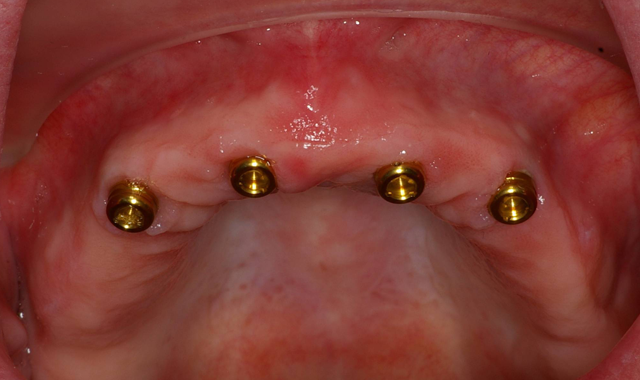

A baseline ISQ reading was taken of these implants utilizing the Penguin RFA (Aseptico). Since the initial readings were all above 70, 3 mm height LOCATOR attachments (ZEST Dental Solutions) were tightened into the dental implants (Fig. 6).

The patient’s existing maxillary denture was relieved in the areas of the attachments (Fig. 7) to avoid putting direct pressure on the implants. The implants were allowed to heal for about four months, at which point impressions would be taken to start fabrication of the definitive prosthesis. Utilizing Panasil® monophase Medium (Kettenbach USA) body impression material in a thermoplastic tray (Fig. 8), a full-arch impression was taken of the maxillary arch picking up the LOCATOR Impression Copings (ZEST Dental Solutions).